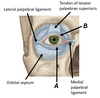

Name ligaments A and B

A - Superior tarsus ligament

B - Inferior tarsus ligament

Name structures A and B

A - Common tendinous ring

B - Trochlea